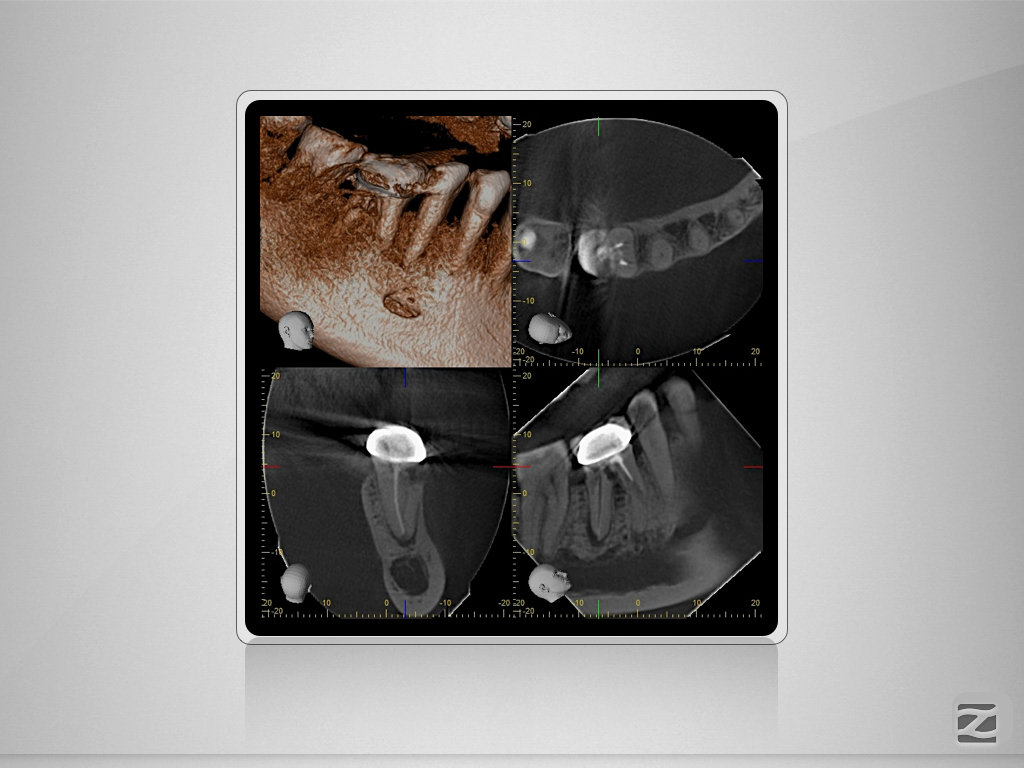

46D.004

2D vs. 3D (XXVIV)